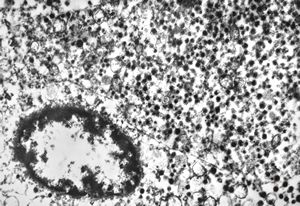

M, 38y. | pheochromocytoma

M, 62y. | pheochromocytoma